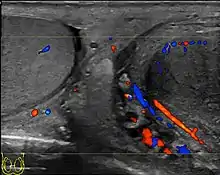

At ultrasound, the findings of acute epididymitis include an enlarged hypoechoic or hyperechoic (presumably secondary to hemorrhage) epididymis [Fig. 20a]. Other signs of inflammation such as increased vascularity, reactive hydrocele, pyocele and scrotal wall thickening may also be present. Testicular involvement is confirmed by the presence of testicular enlargement and an inhomogeneous echotexture. Hypervascularity on color Doppler images [Fig. 20b] is a well-established diagnostic criterion and may be the only imaging finding of epididymo-orchitis in some men.

Doppler ultrasound of epididymitis, seen as a substantial increase in blood flow in the left epididymis (top image), while it is normal in the right (bottom image). The thickness of the epididymis (between yellow crosses) is only slightly increased (7 mm).